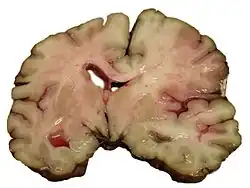

Intracerebral hemorrhage

It generally occurs in small arteries or arterioles and is commonly due to hypertension,[58] intracranial vascular malformations (including cavernous angiomas or arteriovenous malformations), cerebral amyloid angiopathy, or infarcts into which secondary hemorrhage has occurred.[2] Other potential causes are trauma, bleeding disorders, amyloid angiopathy, illicit drug use (e.g., amphetamines or cocaine). The hematoma enlarges until pressure from surrounding tissue limits its growth, or until it decompresses by emptying into the ventricular system, CSF or the pial surface. A third of intracerebral bleed is into the brain's ventricles. ICH has a mortality rate of 44 percent after 30 days, higher than ischemic stroke or subarachnoid hemorrhage (which technically may also be classified as a type of stroke[2]).

Hemorrhagic

Hemorrhagic stroke is classified based on their underlying pathology. Some causes of hemorrhagic stroke are hypertensive hemorrhage, ruptured aneurysm, ruptured AV fistula, transformation of prior ischemic infarction, and drug-induced bleeding.[74] They result in tissue injury by causing compression of tissue from an expanding hematoma or hematomas. In addition, the pressure may lead to a loss of blood supply to affected tissue with resulting infarction, and the blood released by brain hemorrhage appears to have direct toxic effects on brain tissue and vasculature.[53][75] Inflammation contributes to the secondary brain injury after hemorrhage.[75]